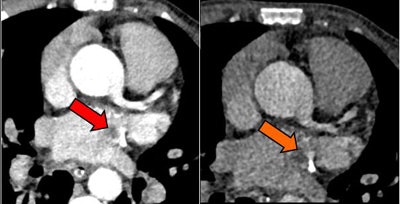

Above, an adult with indeterminate vasculitis that was unreported on echocardiography and seen on CT as mural aortic thickening (orange arrow) with extension into arch vessels (red arrow). Below, an adult with a left atrial appendage tip thrombus that was missed on CT and subsequently detected on echocardiography. The abnormality was noted on CT in retrospect (red arrow).Study limitations included its retrospective and single-center design. In addition, the researchers relied on echocardiography reports, and most of the echo was transthoracic echocardiography, Ajlan said.